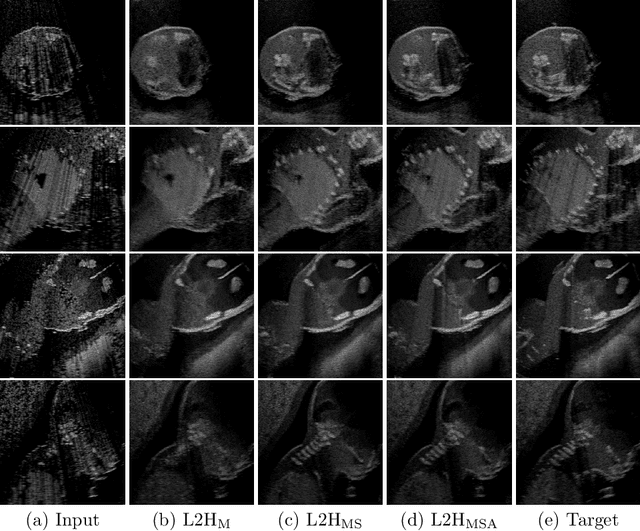

Abstract:Interactive simulation of ultrasound imaging greatly facilitates sonography training. Although ray-tracing based methods have shown promising results, obtaining realistic images requires substantial modeling effort and manual parameter tuning. In addition, current techniques still result in a significant appearance gap between simulated images and real clinical scans. In this work we introduce a novel image translation framework to bridge this appearance gap, while preserving the anatomical layout of the simulated scenes. We achieve this goal by leveraging both simulated images with semantic segmentations and unpaired in-vivo ultrasound scans. Our framework is based on recent contrastive unpaired translation techniques and we propose a regularization approach by learning an auxiliary segmentation-to-real image translation task, which encourages the disentanglement of content and style. In addition, we extend the generator to be class-conditional, which enables the incorporation of additional losses, in particular a cyclic consistency loss, to further improve the translation quality. Qualitative and quantitative comparisons against state-of-the-art unpaired translation methods demonstrate the superiority of our proposed framework.